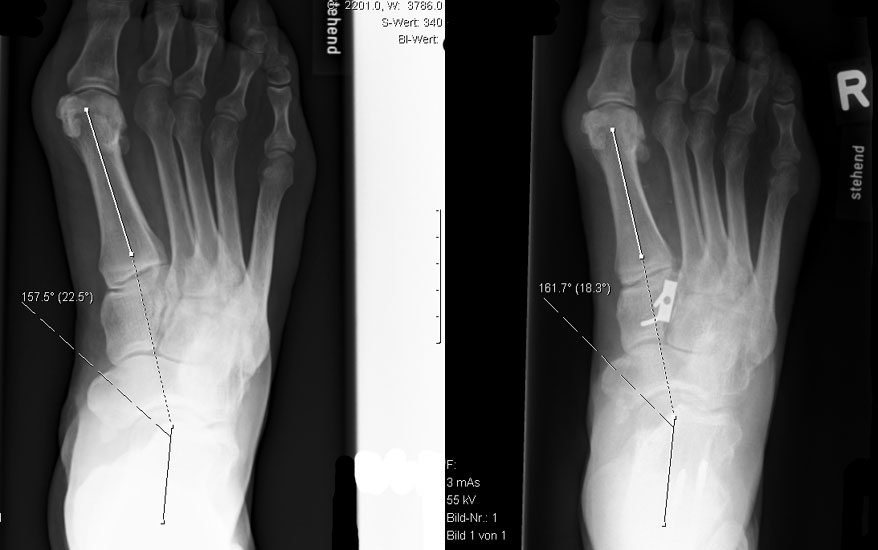

Release der Plantarfaszie (“Operation nach Steindler”) (Abb. 12 und 13, Video 6)

Unzureichende Korrektur des ausgeprägt hohen medialen Längsgewölbe nach dorsalflektierender MT I (bis III) Osteotomie und Peroneus longus auf brevis Transfer aufgrund einer kontrakten Plantarfaszie.

Die Veränderung findet sich gehäuft bei Hohlfüßen mit neurologischer Ätiologie.

Die kontrakte Plantarfaszie trägt sowohl zur Aufrechterhaltung des Längsgewölbes, als auch zum Rückfuβ varus individuell unterschiedlich bei (Abb. 12). Solange die Hohlfuβ-Deformität noch flexibel ist, kann vom Release eine zusätzliche Korrektur erwartet werden (Steindler 1917.). Auch in Kombination mit dorsalflektierender MT I (bis III) Osteotomie und Peroneus longus auf brevis Transfer ist in der Literatur eine Überkorrektur mit Entwicklung eines Pes planovalgus unbekannt.

• Durchtrennen der Plantarfaszie am Ursprung; Spannung der Faszie mittels Dorsalflexion der Zehen in den MTP Gelenken erleichtert die Durchtrennung und das Erkennen tiefer gelegener Septen, welche ebenfalls mit grosser Vorsicht wegen der unmittelbaren Nähe zum N. plantaris lateralis durchtrennt werden sollten (Abb. 12).